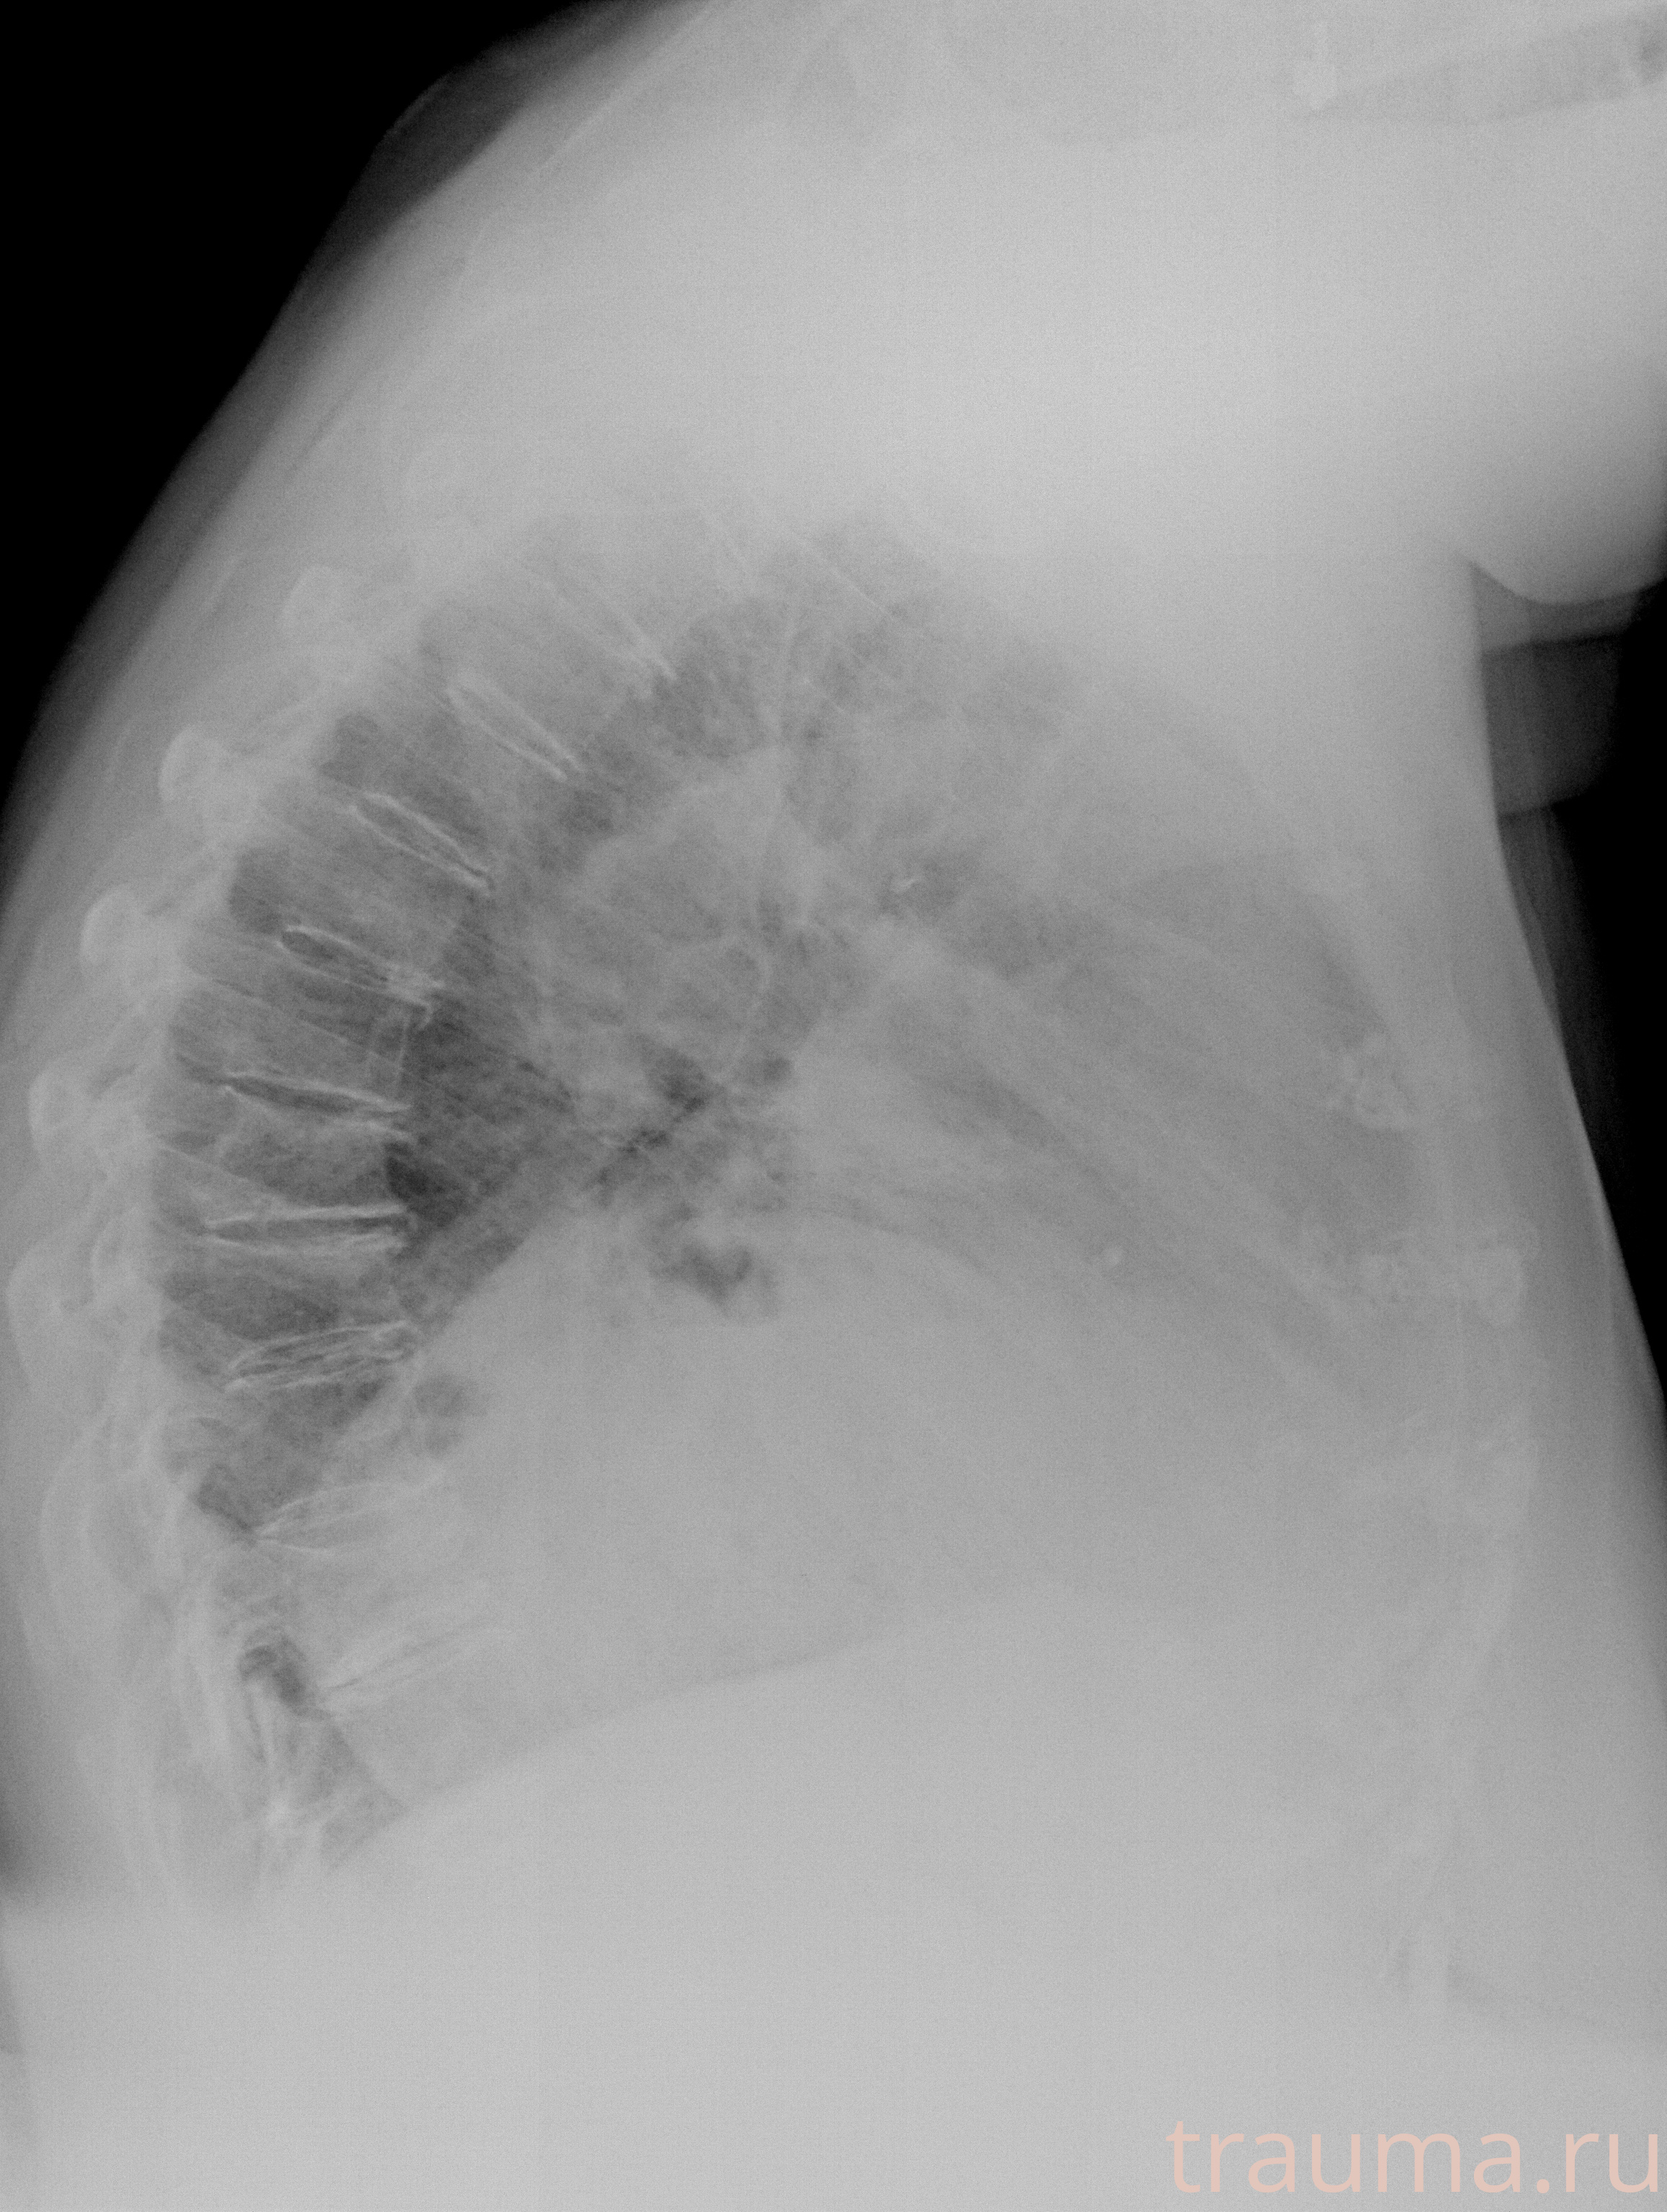

Рентгенограммы

Рентген на дому: по вашему адресу приезжает врач-рентгенолог, травматолог-ортопед с мобильным рентгеновским аппаратом, проводит диагностику травмы или заболевания, делает необходимые рентгенограммы, дает рекомендации по дальнейшему лечению. Получить качественные снимки в домашних условиях возможно благодаря уникальной методике, разработанной МосРентген Центром для института  Склифосовского

при переломе шейки бедра и пневмонии от компании МосРентген Центр - партнера Института имени Склифосовского